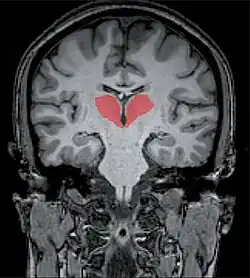

![]() Vista del tálamo en color rojo. | ||

El tálamo es una estructura que se encuentra situada en el centro del encéfalo, por encima del hipotálamo. Forma parte del diencéfalo, del que constituye alrededor del 80%.

El tálamo es una estructura par con forma ovalada. Mide alrededor de 3 cm de largo y representa el 80% del diencéfalo, el 20% restante lo forma el hipotálamo y el epitálamo. Está constituido por núcleos de sustancia gris dispuestos entre tractos de sustancia blanca. Lo atraviesa en toda su longitud una estructura vertical que recibe el nombre de lámina medular interna que lo divide en dos partes y está formada por sustancia blanca que conecta los núcleos talámicos entre sí. El tálamo del lado derecho se une con el izquierdo mediante la comisura gris intertalámica que actúa como un puente entre ambas formaciones.[1]